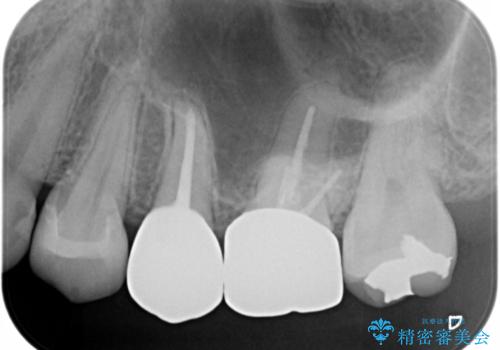

- 笑うと銀歯が目立って気になると来院された方です。まずは外から見えやすいところから治療を開始しました。

- セラミックインレー7万円・仮歯1万円・フルジルコニアクラウン7万円(精密根管治療は別途)費用は治療当時の料金となります

根管治療をした歯は神経のある歯と比較して強度が下がり、長期的に破折のリスクが高まると言われています。破折のリスクを軽減させるため、根管治療を行った歯に対しては歯冠をすべて覆うクラウンという被せ物にて補綴処置を行います。

適合不良の補綴物は二次的な虫歯発生のリスクが高まります。

自費診療で用いられる材料は保険適応の材料に比べて、より精密で適合の良い被せ物作ることができるため、長期的な虫歯のリスクを大幅に減らすことが可能です。